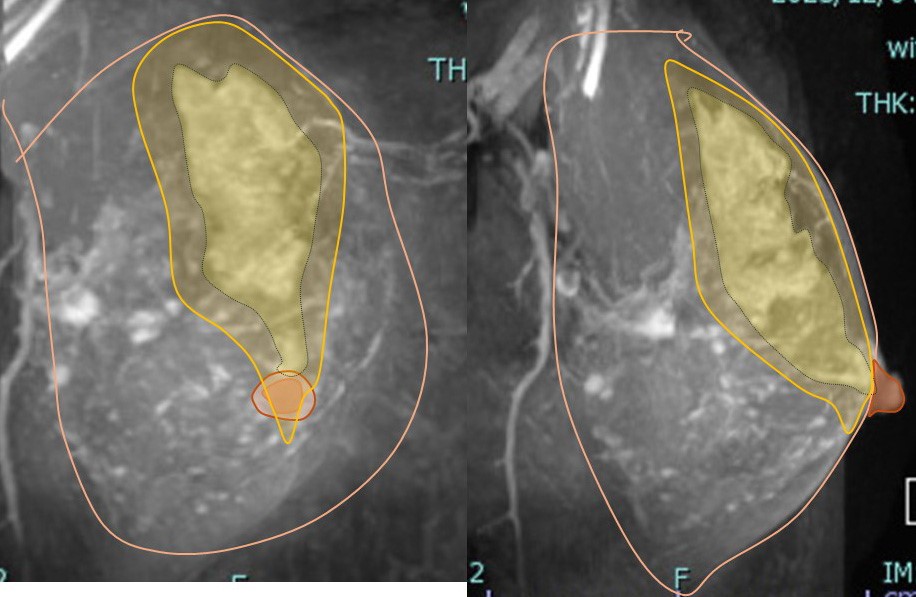

1. 画像所見

MMGで壊死型石灰化の範囲は68mm MRIでの拡がり

3. 病変に対する(マージンをつけた)切除範囲

乳頭を超えた切除としていますが、乳頭は皮膚を含めて切除しません。

♯側面で見るとよくわかります。